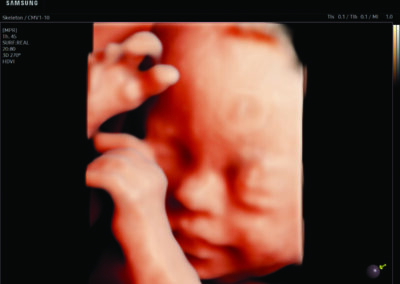

Comprehensive, advanced and expert MFM care for high-risk pregnancies